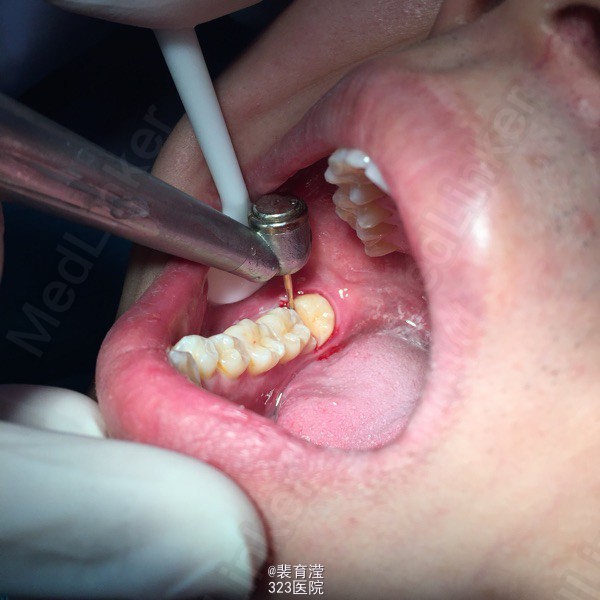

诊断:异物囊肿 右下第三磨牙阻生 处理:1.局麻下切除异物囊肿,缝合,止血。 2.右下第三磨牙局麻下 拔除 搔刮牙槽窝 止血。

随访:口服消炎药 ,止疼药后无不适,一周后拆线 讨论:阻生齿拔除 先去处阻力。